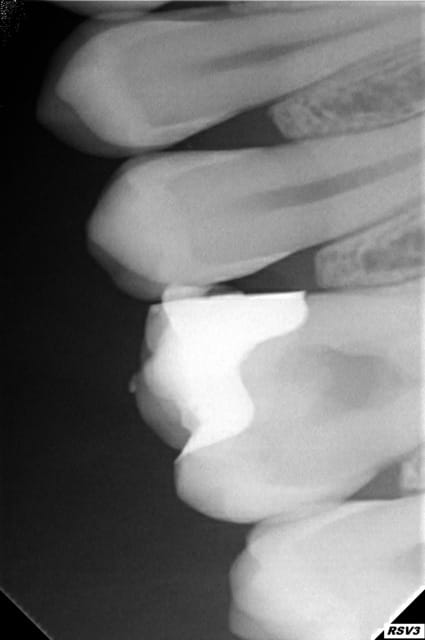

Patiente de 21 ans arrive avec une hyperémie de la 26. je pose de la biodentine et je lui fait un devis pour un inlay (à 235 euros). Je viens de me mettre aux inlays et au concept de garder la dent vivante (j'ai fait la journée de formation avec cingulum à clinic all).

On avait perdu une partie de la cuspide mv et de la mp et un inlay était indiqué je pense.

Déjà dans ce cas je suis tomber sur une grande effraction pulpaire. Apparemment il n'y a que la biodentine qui marche, l'hydroxyde de calcium n'étant pas suffisant (la prochaine fois je ferai un devis de 50 euros hn pour mettre la biodentine quitte à revoir le patient une prochaine fois...)

Je pense que je n'étais pas assez sur de l'intérêt d'un inlay par rapport à un composite. Je n'ai pas de recul pour pouvoir comparer les deux et dans ma tête si il n'y a pas du tout de salive, un collage correct et pleins de couches cela vaut pratiquement l'inlay : c'est pour ça que je n'ai pas insisté.

Une piste de réflexion sur l'avantage de l'inlay serai que comme on est déjà proche de la pulpe, une reprise carieuse serait beaucoup plus embêtante que sur une petite carie. Quand le compo se sera détérioré on va aller plus vite vers une couronne....

Ah bon bah dans ce cas c'est différent, tu as mal présenté les choses, c'était pas composite ou inlay, c'était soit le patient veut garder sa dent vivante et c'est biodentine et inlay, soit il veut du tout remboursé et c'est endo couronne.

Biodentine sous un composite c'est un non sens absolu. Théoriquement tu pourrais proposer un devis pour la biodentine et faire un superbe composite dessus, mais ça resterait une solution de compromis un peu triste... Soit le patient et toi vous décidez de mettre les moyens et alors c'est biodentine + inlay, soit vous décidez de ne pas les mettre et c'est ni l'un ni l'autre, mais entre les deux ça n'a pas vraiment de sens à mon avis, ni pour lui ni pour toi.